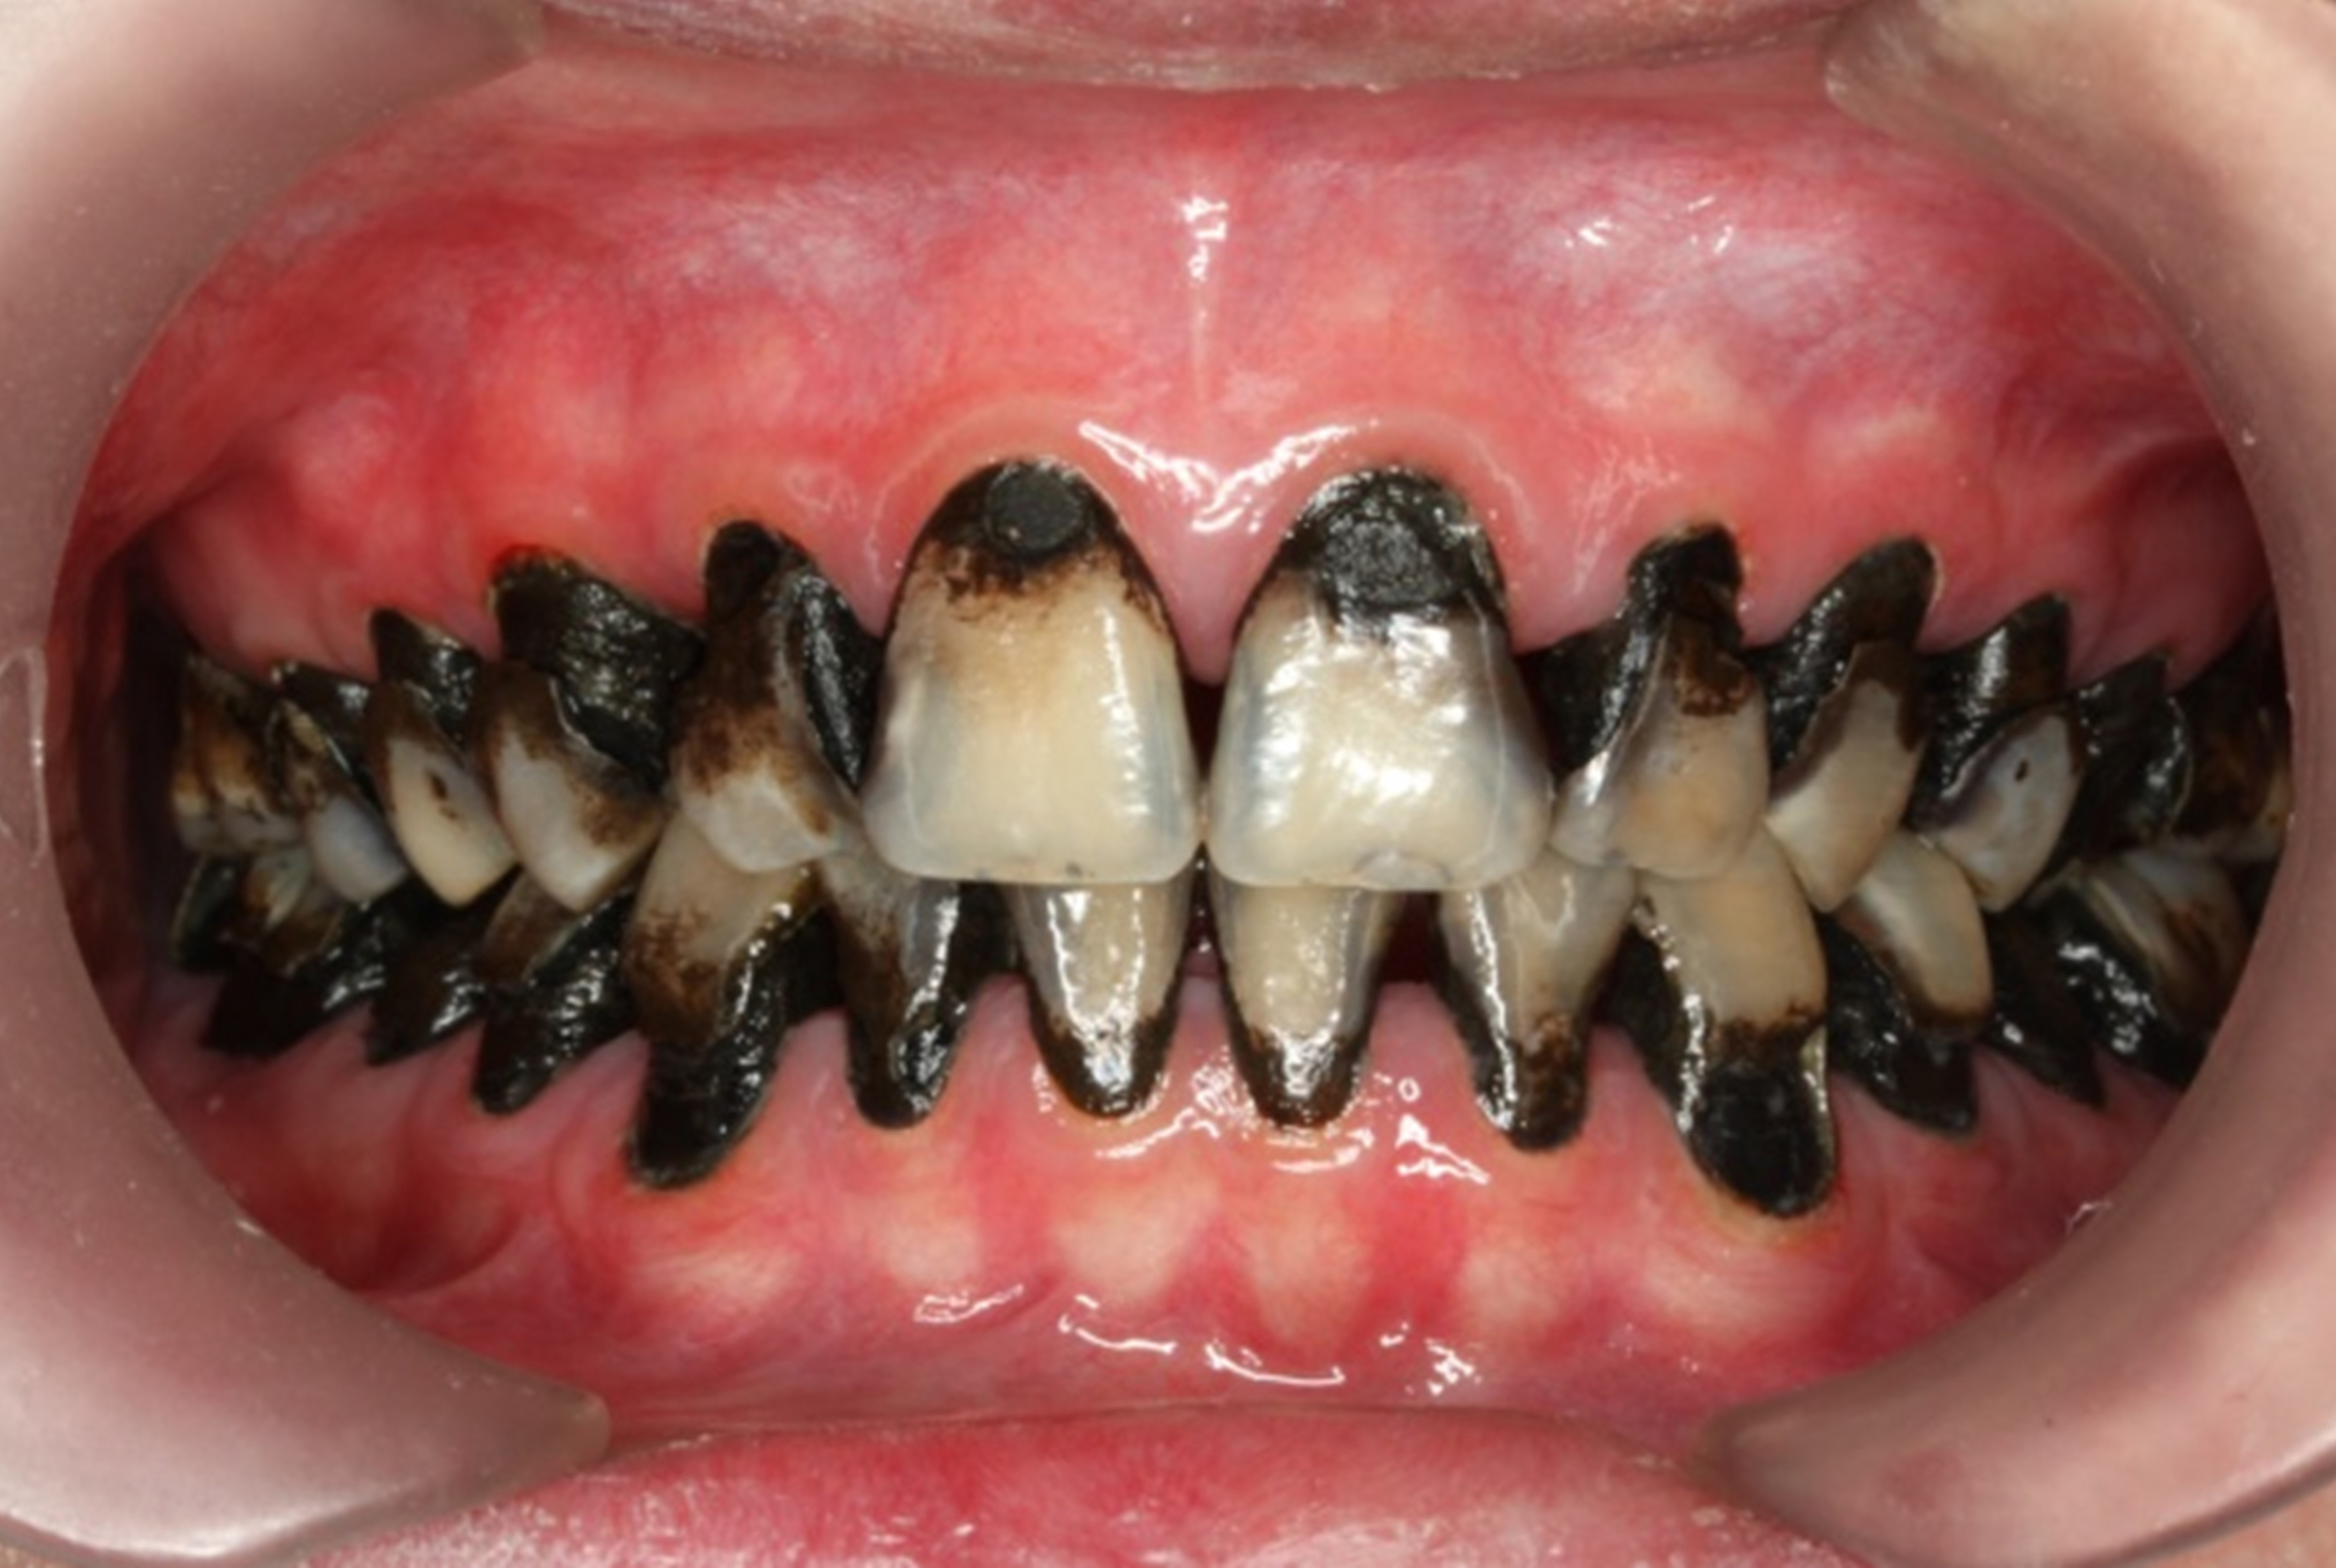

The inherent disadvantage of SDF is that the caries lesions will be stained black after SDF application. SDF stops caries progression by forming a hard, blackened, impermeable layer on the tooth surface that is resistant to caries (Figure 5 through Figure 9). The authors’ clinical observations are that the darker the color, the more likely the caries arrested. Some patients may not be pleased with the esthetics of this treatment outcome; therefore, it is important to inform the patients and parents (for child patients) about this treatment outcome. Moreover, SDF can stain clothes and the skin of the body. Though it does not cause any pain or damage, an SDF stain on skin cannot be easily washed away. It takes around 7 days for it to disappear, and the stain on clothes is permanent.22

There is no consensus on the frequency of application, and 38% SDF has been used annually or biannually on clinical trials in children23,31,33,34 and in elderly.30,35 Yee and his co-worker found one-off application of 12% SDF was ineffective in arresting caries in children.31 The present authors applied 38% SDF weekly for 3 weeks to speed up the process of caries arrest and for treatment of rampant caries.36 One of the present authors’ case reports demonstrated that three weekly applications of 38% SDF can arrest rampant caries and relieve pain from hypersensitivity on a teenager. The SDF-treated caries were found arrested, and they turned coal black in appearance (Figure 9).

Fig 8. Use of 38% SDF to arrest rampant caries in a young teenager: pre-treatment intraoral frontal view of rampant caries. (image from Chu, et al, 2014, ref 36 [reprinted with approval])

Figure 8